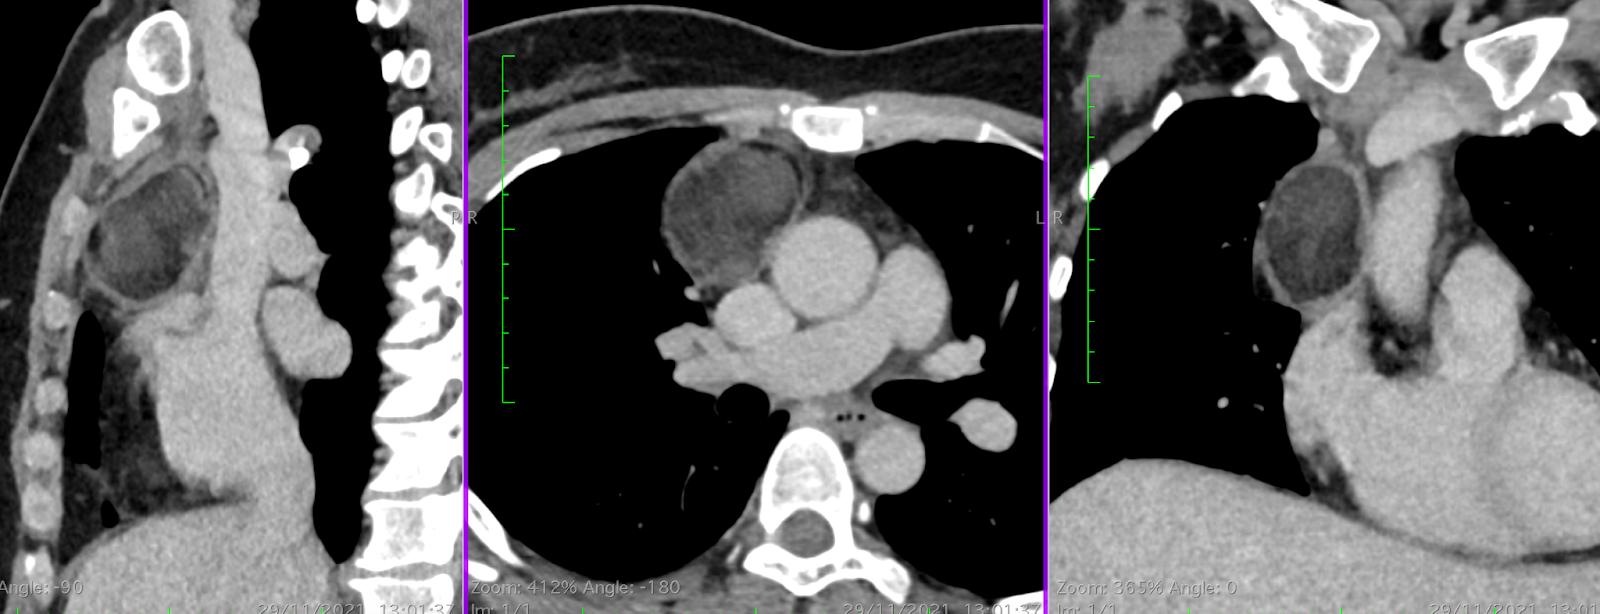

Là người trực tiếp thăm khám và điều trị cho bà Hoa, TS, BS Nguyễn Anh Dũng, Trưởng khoa Phẫu thuật Tim mạch-Lồng ngực, cho biết, khối u trung thất của bệnh nhân có cấu tạo rất lạ gồm cả lông, tóc, xương…, được gọi là “u quái”.

Khối u có đường kính hơn 5cm, bắt đầu chèn ép các tĩnh mạch chủ trên và động mạch chủ chung quanh. Nếu khối u tiếp tục phát triển sẽ cản trở máu từ tĩnh mạch chủ trên đi xuống, gây ra triệu chứng phù (hội chứng tĩnh mạch chủ trên). Vì thế, cần phẫu thuật ngay thời điểm này để loại bỏ hoàn toàn khối u quái, tránh những rủi ro sức khỏe sau này.

Bác sĩ Dũng cho biết, khó khăn lớn nhất trong ca mổ là khối u nằm gần tĩnh mạch chủ, động mạch chủ và khí quản. Nếu thao tác mổ không thuần thục, các đường bóc tách không chính xác thì sẽ làm tổn thương mạch máu, thậm chí ảnh hưởng đến đường thở, nguy hiểm tính mạng.